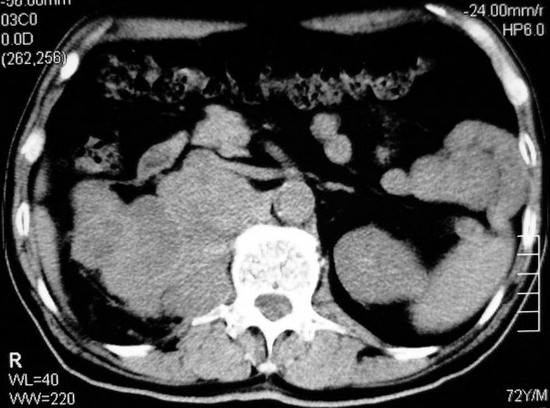

以下是引用杀毒软件在2008-11-17 19:15:00的发言:[br]考虑------右肾癌合并肾静脉---同侧肾上腺受侵可能性大

以下是引用zjzjr在2008-11-17 20:45:00的发言:[br]考虑------右肾癌合并肾静脉---同侧肾上腺受侵可能性大及腹膜后淋巴结转移.